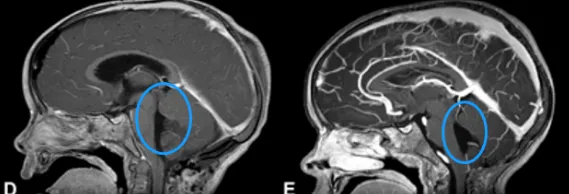

手术那天,安安的家人在手术室外焦急等待,只希望孩子能平安出来。最后的结果,却让他们喜出望外。Rutka教授采用枕下开颅联合C1椎板切除术,成功将巨大室管膜瘤全切,手术过程中没有出现神经功能损伤。术后病理确认为间变性室管膜瘤。

经历了这场惊心动魄的手术,安安恢复很快,术后3年的多次复查均未见复发,生活一如往常。